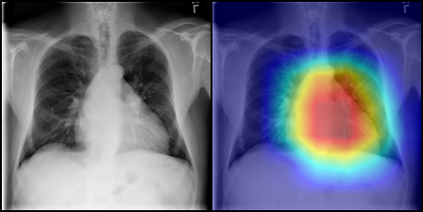

In this work, we present an end-to-end deep learning framework for X-ray image diagnosis. As the first step, our system determines whether a submitted image is an X-ray or not. After it classifies the type of the X-ray, it runs the dedicated abnormality classification network. In this work, we only focus on the chest X-rays for abnormality classification. However, the system can be extended to other X-ray types easily. Our deep learning classifiers are based on DenseNet-121 architecture. The test set accuracy obtained for 'X-ray or Not', 'X-ray Type Classification', and 'Chest Abnormality Classification' tasks are 0.987, 0.976, and 0.947, respectively, resulting into an end-to-end accuracy of 0.91. For achieving better results than the state-of-the-art in the 'Chest Abnormality Classification', we utilize the new RAdam optimizer. We also use Gradient-weighted Class Activation Mapping for visual explanation of the results. Our results show the feasibility of a generalized online projectional radiography diagnosis system.